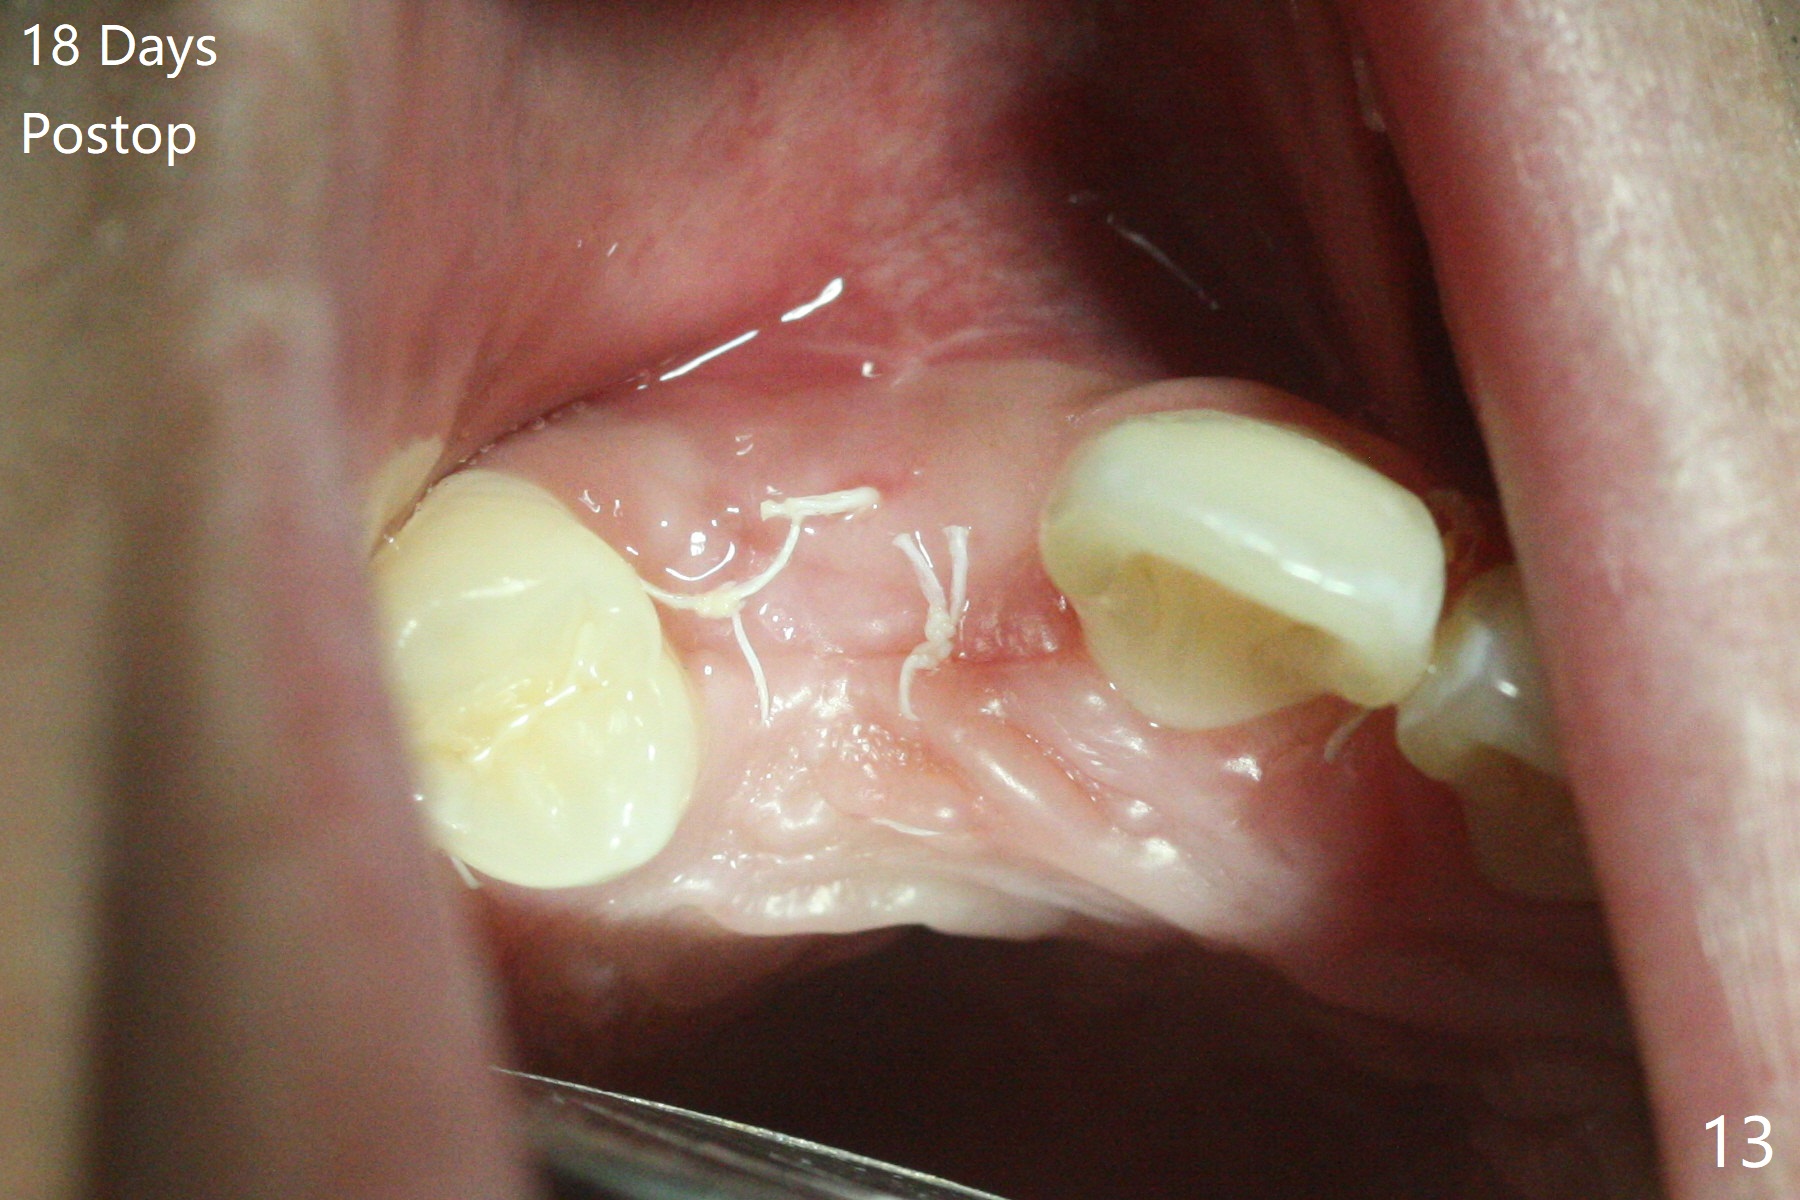

18岁男从外州大学回来,无症状,但是6号牙(右上尖牙)颊侧瘘道(图一,二(角化龈充分(箭头))),根尖片显示植体近中骨吸收(图三:*),而对侧植体仿佛骨整合(图四)。患侧切开后发现植体颊侧暴露,松动。拔除后骨缺损由粘性骨粉修复(图七,九:*),覆盖PRF膜(图七:P)和带钛网(图九:^)不可吸收膜(图五-七),后者用两个小钉子固定(图六(腭侧),七(颊侧),九),使用新的刀片和一个特殊尖头剥离器在颊侧骨膜下相当广泛分离,使用PTFE缝线,粘膜下水平褥式缝合之后(图八:箭头),多个垂直间断缝合,两个乳头垂直褥式缝合。术后一周伤口没有裂开,术后疼痛肿胀已经消退(图十)。术后十八天牙槽嵴仿佛比对侧还要宽(图十一,三与图十二,四(取模)对比)。术后5.5个月伤口没有裂开,牙槽骨,角化龈宽(图十六),与钛网和两个小钉子固定有关(图十五,十七)。CT显示牙槽骨只能容纳2.5或者3.0毫米植体(图十八)。11号牙植体牙冠粘固后没有骨质吸收(图十九),其实10,11号牙颊侧骨板隆起(图二十至二十二),而6植体失败,颊侧骨板吸收,甚至累及5号牙(图十七)。